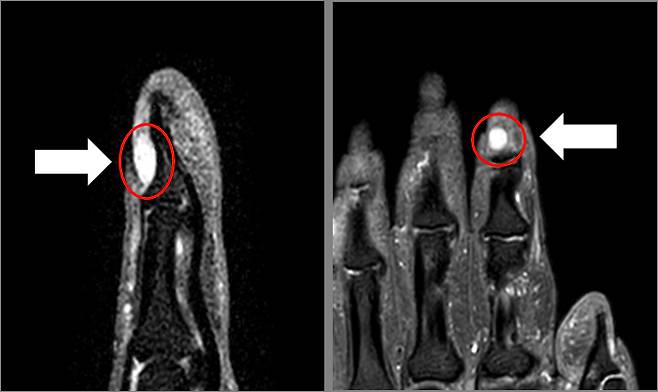

사구체는 피부 온도 조절을 돕는 모세 혈관이 털 뭉치처럼 얽혀 형성된 것으로, 이 사구체에 이상이 생기면 사구체 종양이 된다. 발생 시 손가락과 발가락 끝을 눌렀을 때 심한 압통이 주된 증상으로, 차가운 온도에 민감한 특성을 가진다. 종양 크기는 보통 5mm~1cm 미만으로 미세하기 때문에 초음파 검사로도 발견하기 어려워 MRI 촬영에서 진단되는 경우가 많다. 주로 여성에게 잘 발생하고 아직까지 정확한 원인은 밝혀지지 않았다.

강동성심병원 정형외과 이승진 교수는 “사구체 종양 제거는 손톱을 들고 종양을 절제한 후 손톱 바닥을 복원하는 수술로 30분 정도 소요가 되는 비교적 간단한 수술이다.”며 “흔하지 않은 양성 종양이라 진단이 어렵지만, 방치할 경우 드물게 종양이 커지면서 손가락 뼈의 함몰이나 변형이 발생할 수 있으니 통증이 심하다면 참지 말고 병원을 방문하여 전문의와의 상담하는 것이 좋다”고 조언했다.